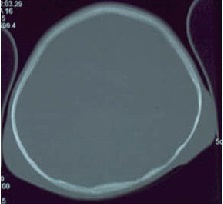

An 18 month old girl born of third degree consanguineous marriage presented with gradual restriction of movements in both the limbs for 6 months. Patient had flexion contractures of both ankles, knees, hips, elbows and limitation of movements of the spine. Pink confluent papules were present on both the ears. Bilateral parietal non-tender fluctuant swellings were seen over the scalp, which were non-transilluminant and progressively increasing in size {Fig 1}. Patient had a mental delay with social quotient of 33. There was no gingival hypertrophy. Skeletal radiography showed joint contractures without any lytic or sclerotic lesion. CT scan of brain revealed soft tissue swelling over both parietal bones. {Fig 2} Histologic examination of skin biopsy of the parietal mass by light microscopy showed minimal hyperkeratosis with entire dermis showing eosinophilic homogenous ground substance with numerous fibroblasts with pericellular halo {Fig 3}.

Fig 2